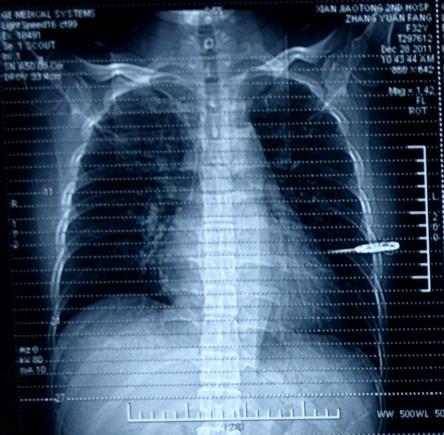

入院第7天的胸部CT:见图3

图3

入院15天后的胸部CT:见图4

图4

曾采取的治疗措施:

第7天开始使用莫西沙星,第10天支气管镜肺泡灌洗,监测患者血常规、降钙素原并留痰培养。